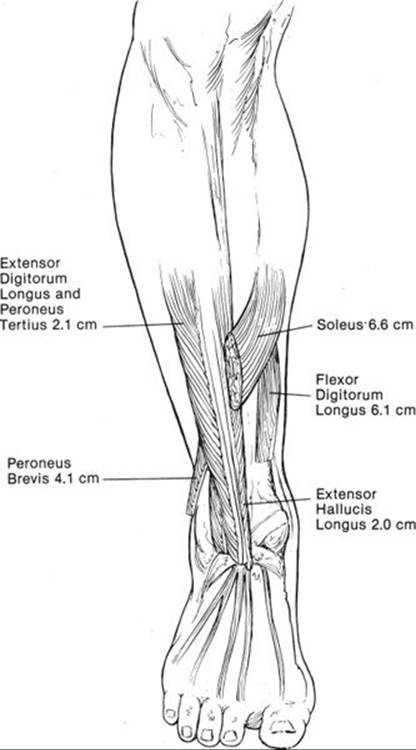

The lower leg muscles make poor pedicled flaps because most of them are type 4 muscles with segmental minor arterial pedicles. As a result, only a small portion of the muscle can safely be transferred without a delay. Although the bulk of these muscles is small, the distal portion of some of these type 4 muscles (Figure 95.4) can be used to cover small defects around the ankle medially, anteriorly, and laterally. To successfully transfer a significant portion of the distal muscle, all the relevant minor perforators are preserved with the accompanying distal major artery and depend on retrograde flow. The sacrifice of a major artery should only be considered if all three arteries are open and there is excellent retrograde flow. It is important to tenodese the distal end of the severed tendon of the harvested muscle to a muscle with similar function so that the harvested muscle’s function is not lost. For example, if the distal muscular-tendinous portion of the extensor hallucis longus (EHL) muscle is harvested, the remaining distal EHL tendon should be tenodesed to the adjacent extensor digitorum longus so that hallux dorsiflexion is not lost. Because the loss of the anterior tibial tendon is so debilitating, this muscle should not be harvested unless the ankle has been or is being fused.

The EHL muscle can cover small defects that are as distal as 2 cm above the medial malleolus. The extensor digitorum longus muscle and peroneus tertius muscle are used for small defects as distal as 2 cm above the medial malleolus. The peroneus brevis muscle can be used for small defects as distal as 4 cm above the medial malleolus. The flexor digitorum longus muscle can be used for small defects as distal as 6 cm above the medial malleolus. The soleus muscle is the only type 2 muscle in the distal lower leg and so the minor distal pedicles can be detached and the muscle can be rotated with its intact proximal major pedicle rotated to cover large (10 cm × 8 cm) anterior lower leg defects as distal as 6.6 cm above the medial malleolus. It can be harvested as a hemisoleus for small defects and as an entire soleus for larger defects. These flaps require skin grafting. In addition, the ankle has to be immobilized to avoid dehiscence and ensure adequate skin graft take. External frames are useful for immobilization and NPWT assist in skin graft take.

FIGURE 95.4. The type 4 muscles of the lower leg are not only thin but can only be harvested for a distance of 2 to 3 segmental pedicles and therefore provide very little bulk to cover lower leg defects. The figure indicates how far proximal from the distal medial malleolus one can expect to find muscle to actually cover small lower leg defects. Fasciocutaneous flaps actually provide more bulk without affecting function. For larger defects a free flap is usually a better option. (From Attinger C. Plastic surgery techniques for foot and ankle surgery. In: Myerson M, ed. Foot and Ankle Disorders. Philadelphia, PA: WB Saunders; 2000:627, with permission.)